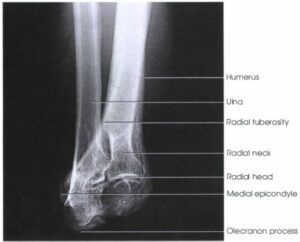

Anatomi

Dirsek eklemi üç ayrı eklemin bir araya gelmesiyle oluşan trochoginglymoid tipte bir eklemdir. Bunlar;

- Radiohumeral; Capitellum ve radius başı arasında.

- Ulnohumeral: Trochlea ve Olekranon arasında.

- Radioulnar: Proksimal radius ve ulna arasında.

Doğumda dirsek eklemi tamamen kıkırdaktır ve radyografilerde bu kıkırdak alana bağlı olarak geniş radyolüsent bir alan görülür. Büyümeyle birlikte kemik dirseği oluşturacak ikincil kemikleşme noktaları ortaya çıkar. Düzgün radyolojik değerlendirmenin yapılabilmesi için bu kemikleşme noktalarının anatomik yapısı ve gelişiminin iyi bilinmesi gereklidir.